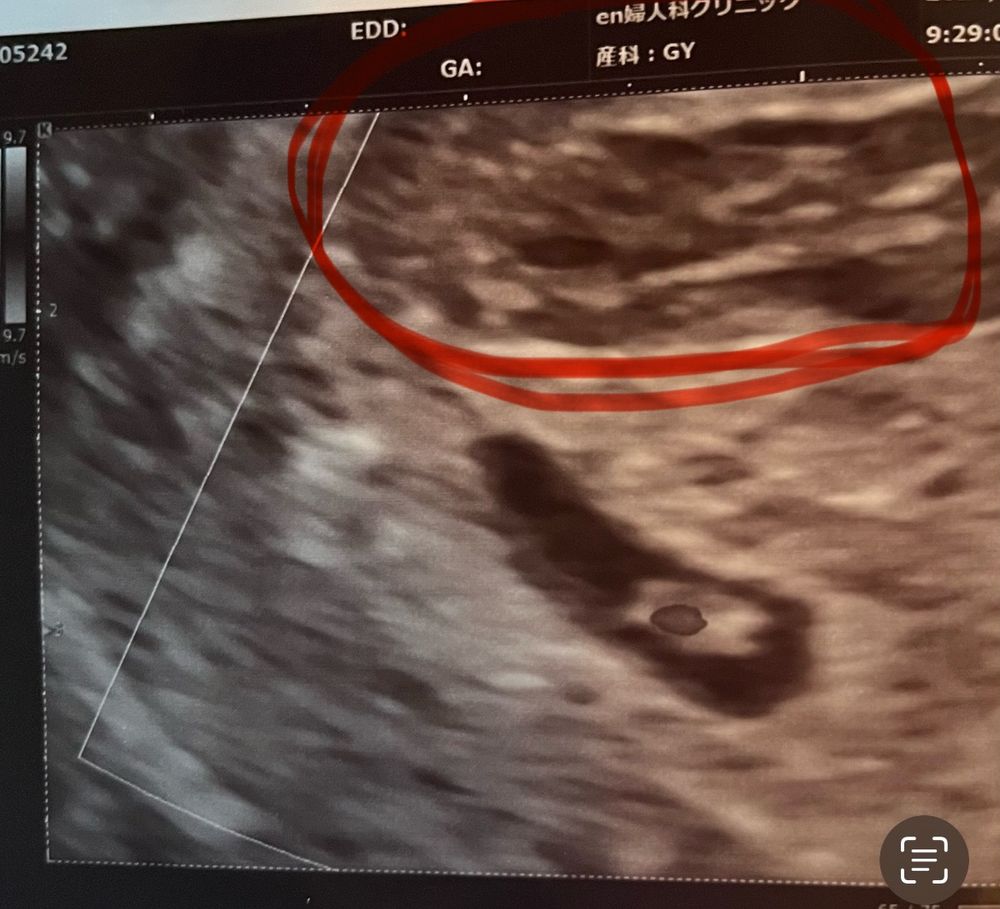

Вопрос знатокам, что кровит? 25 дпп

Ксения, у меня вообще не мажет, только алой кровью льет по 2-4 чайной ложке. Поэтому я сильно тревогу била. Врач не сказала, что именно кровит, вот и пытаюсь понять по снимку узи🤔.

Плодовое яйцо сплющено норма. Если врач сказал, что гематома, да она либо выйдет сгустком коричневым, либо коричневыми выделениями помажет. Появится алая кровь, срочно к врачу. Главное сердечко бьется! Легкой беременности вам!